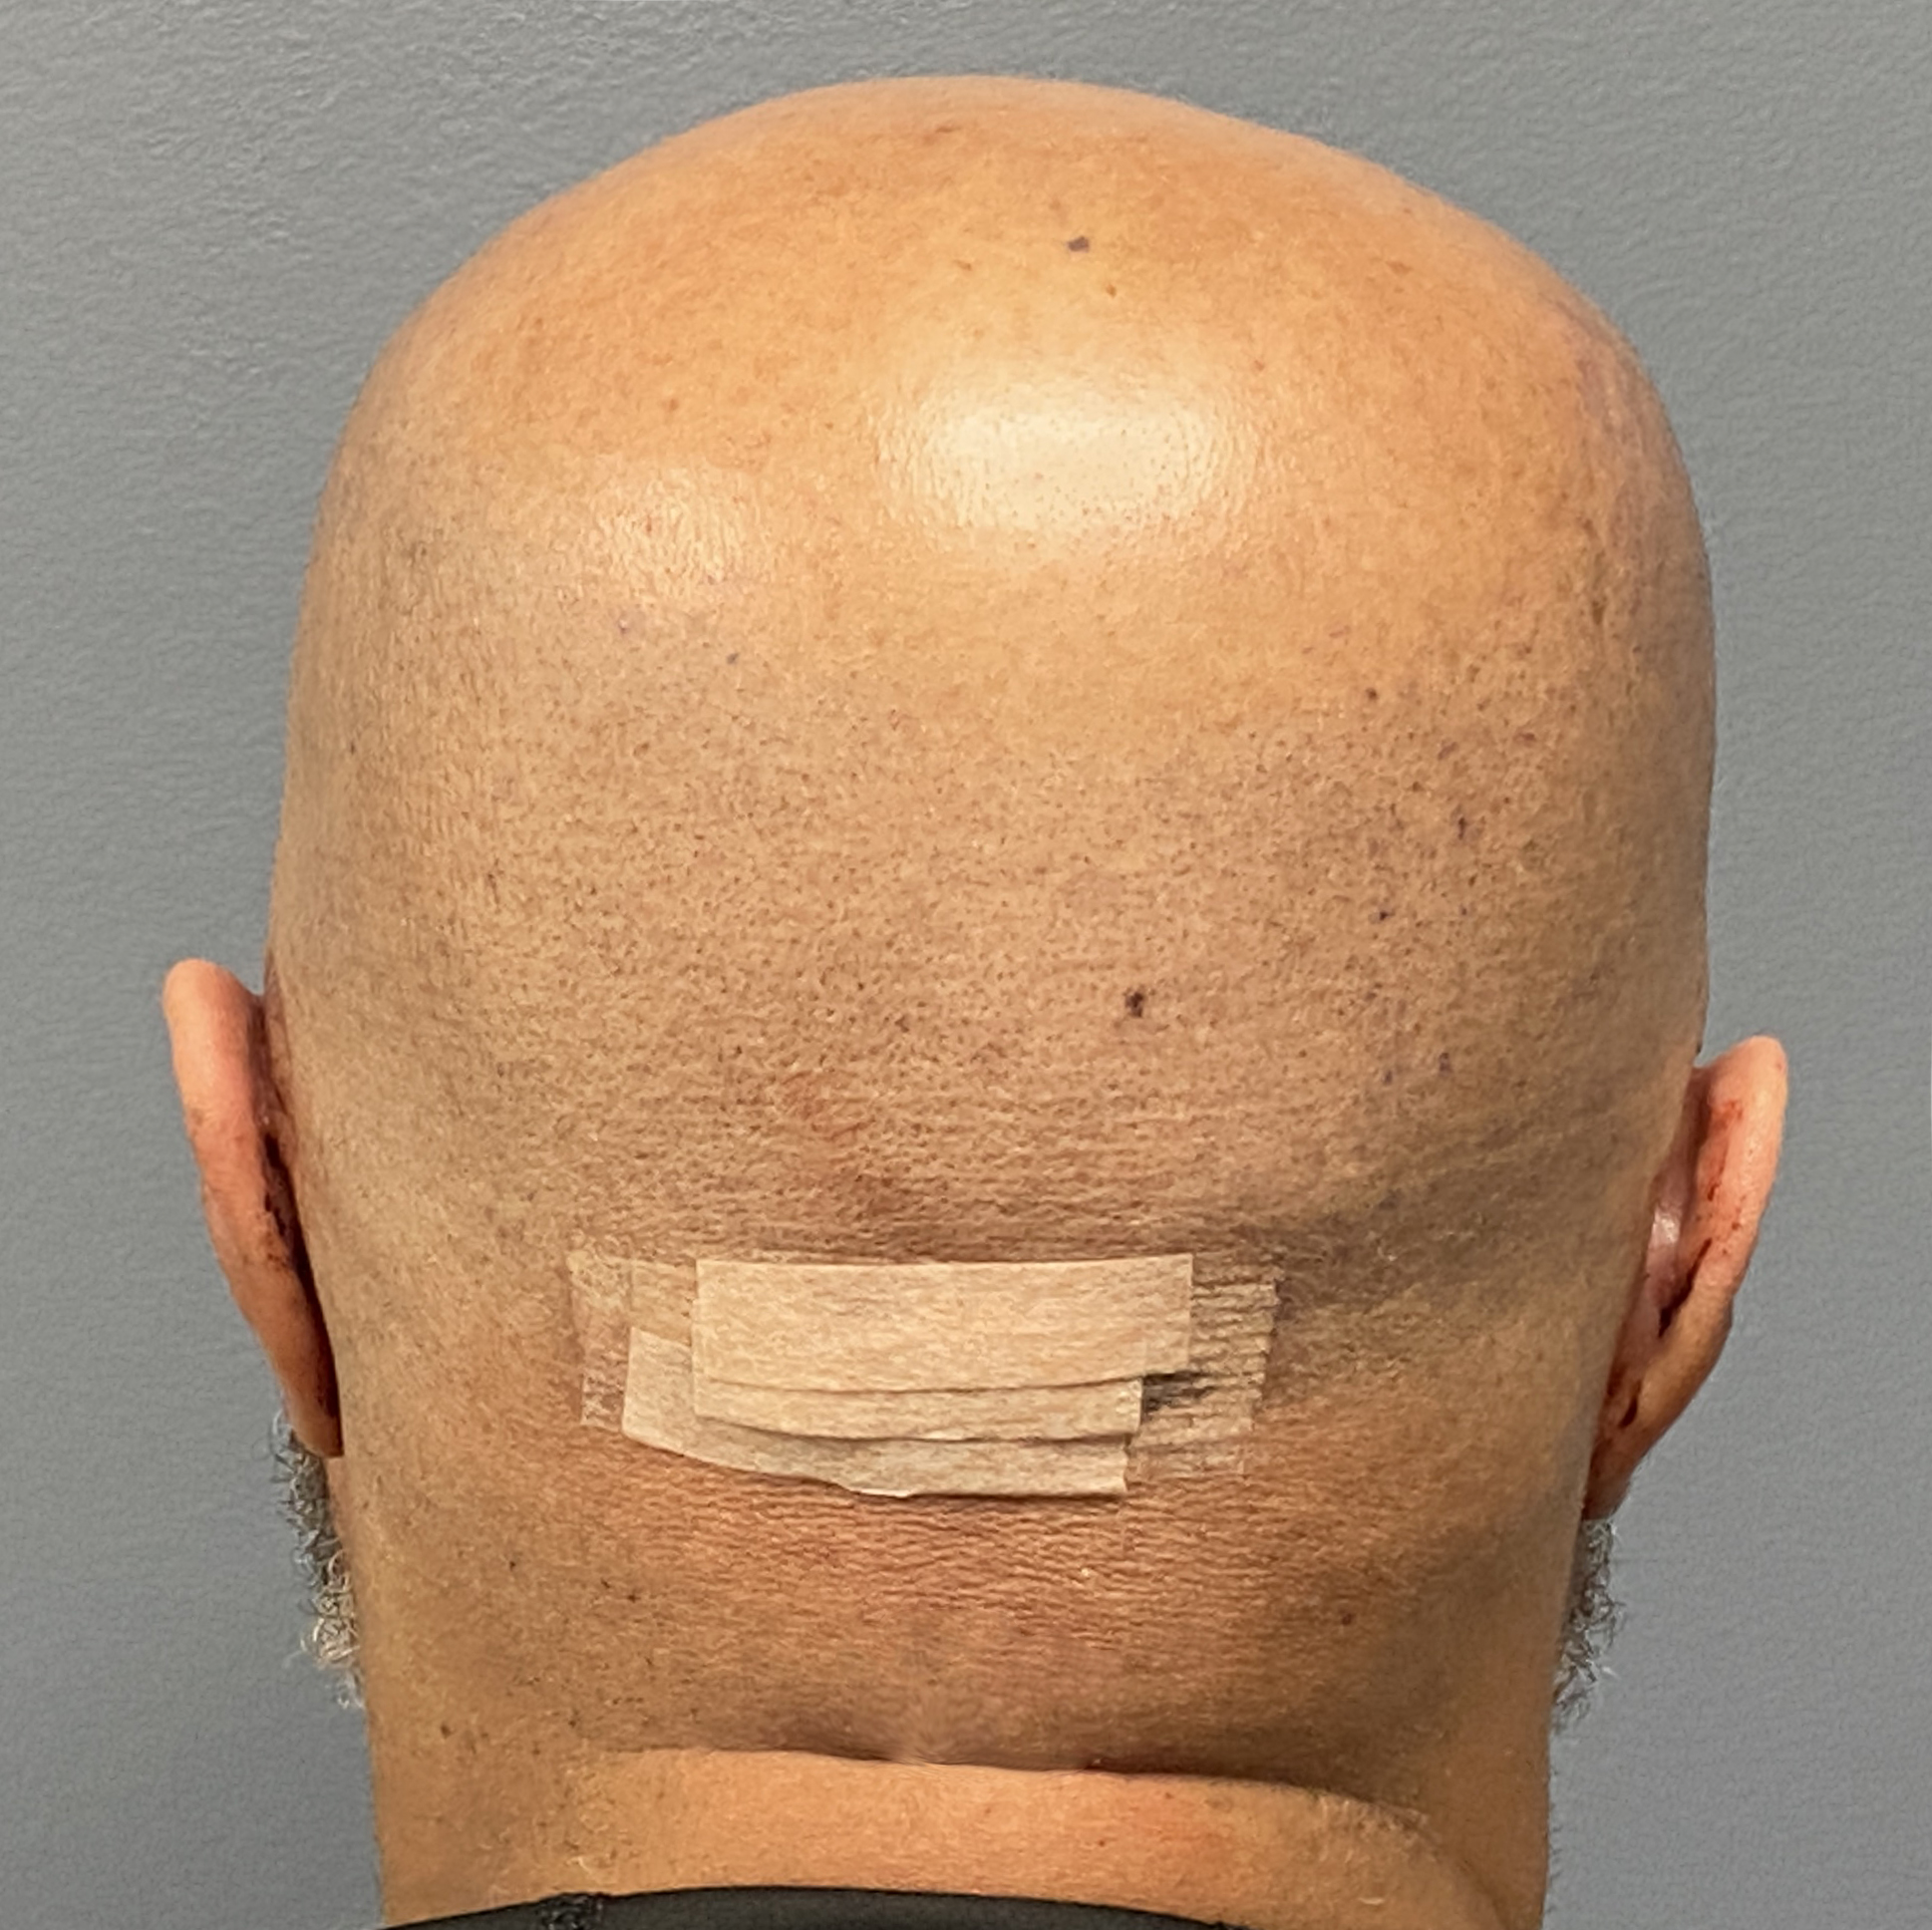

Patient 129

Desire for reduced width/convexity on the sides of his head.

Head narrowing using a temporal muscle transposition technique seen one day postop. He also had an concurrent occipital skull reduction done hence the tape over his incision.

Desire for reduced width/convexity on the sides of his head.

Head narrowing using a temporal muscle transposition technique seen one day postop. He also had an concurrent occipital skull reduction done hence the tape over his incision.